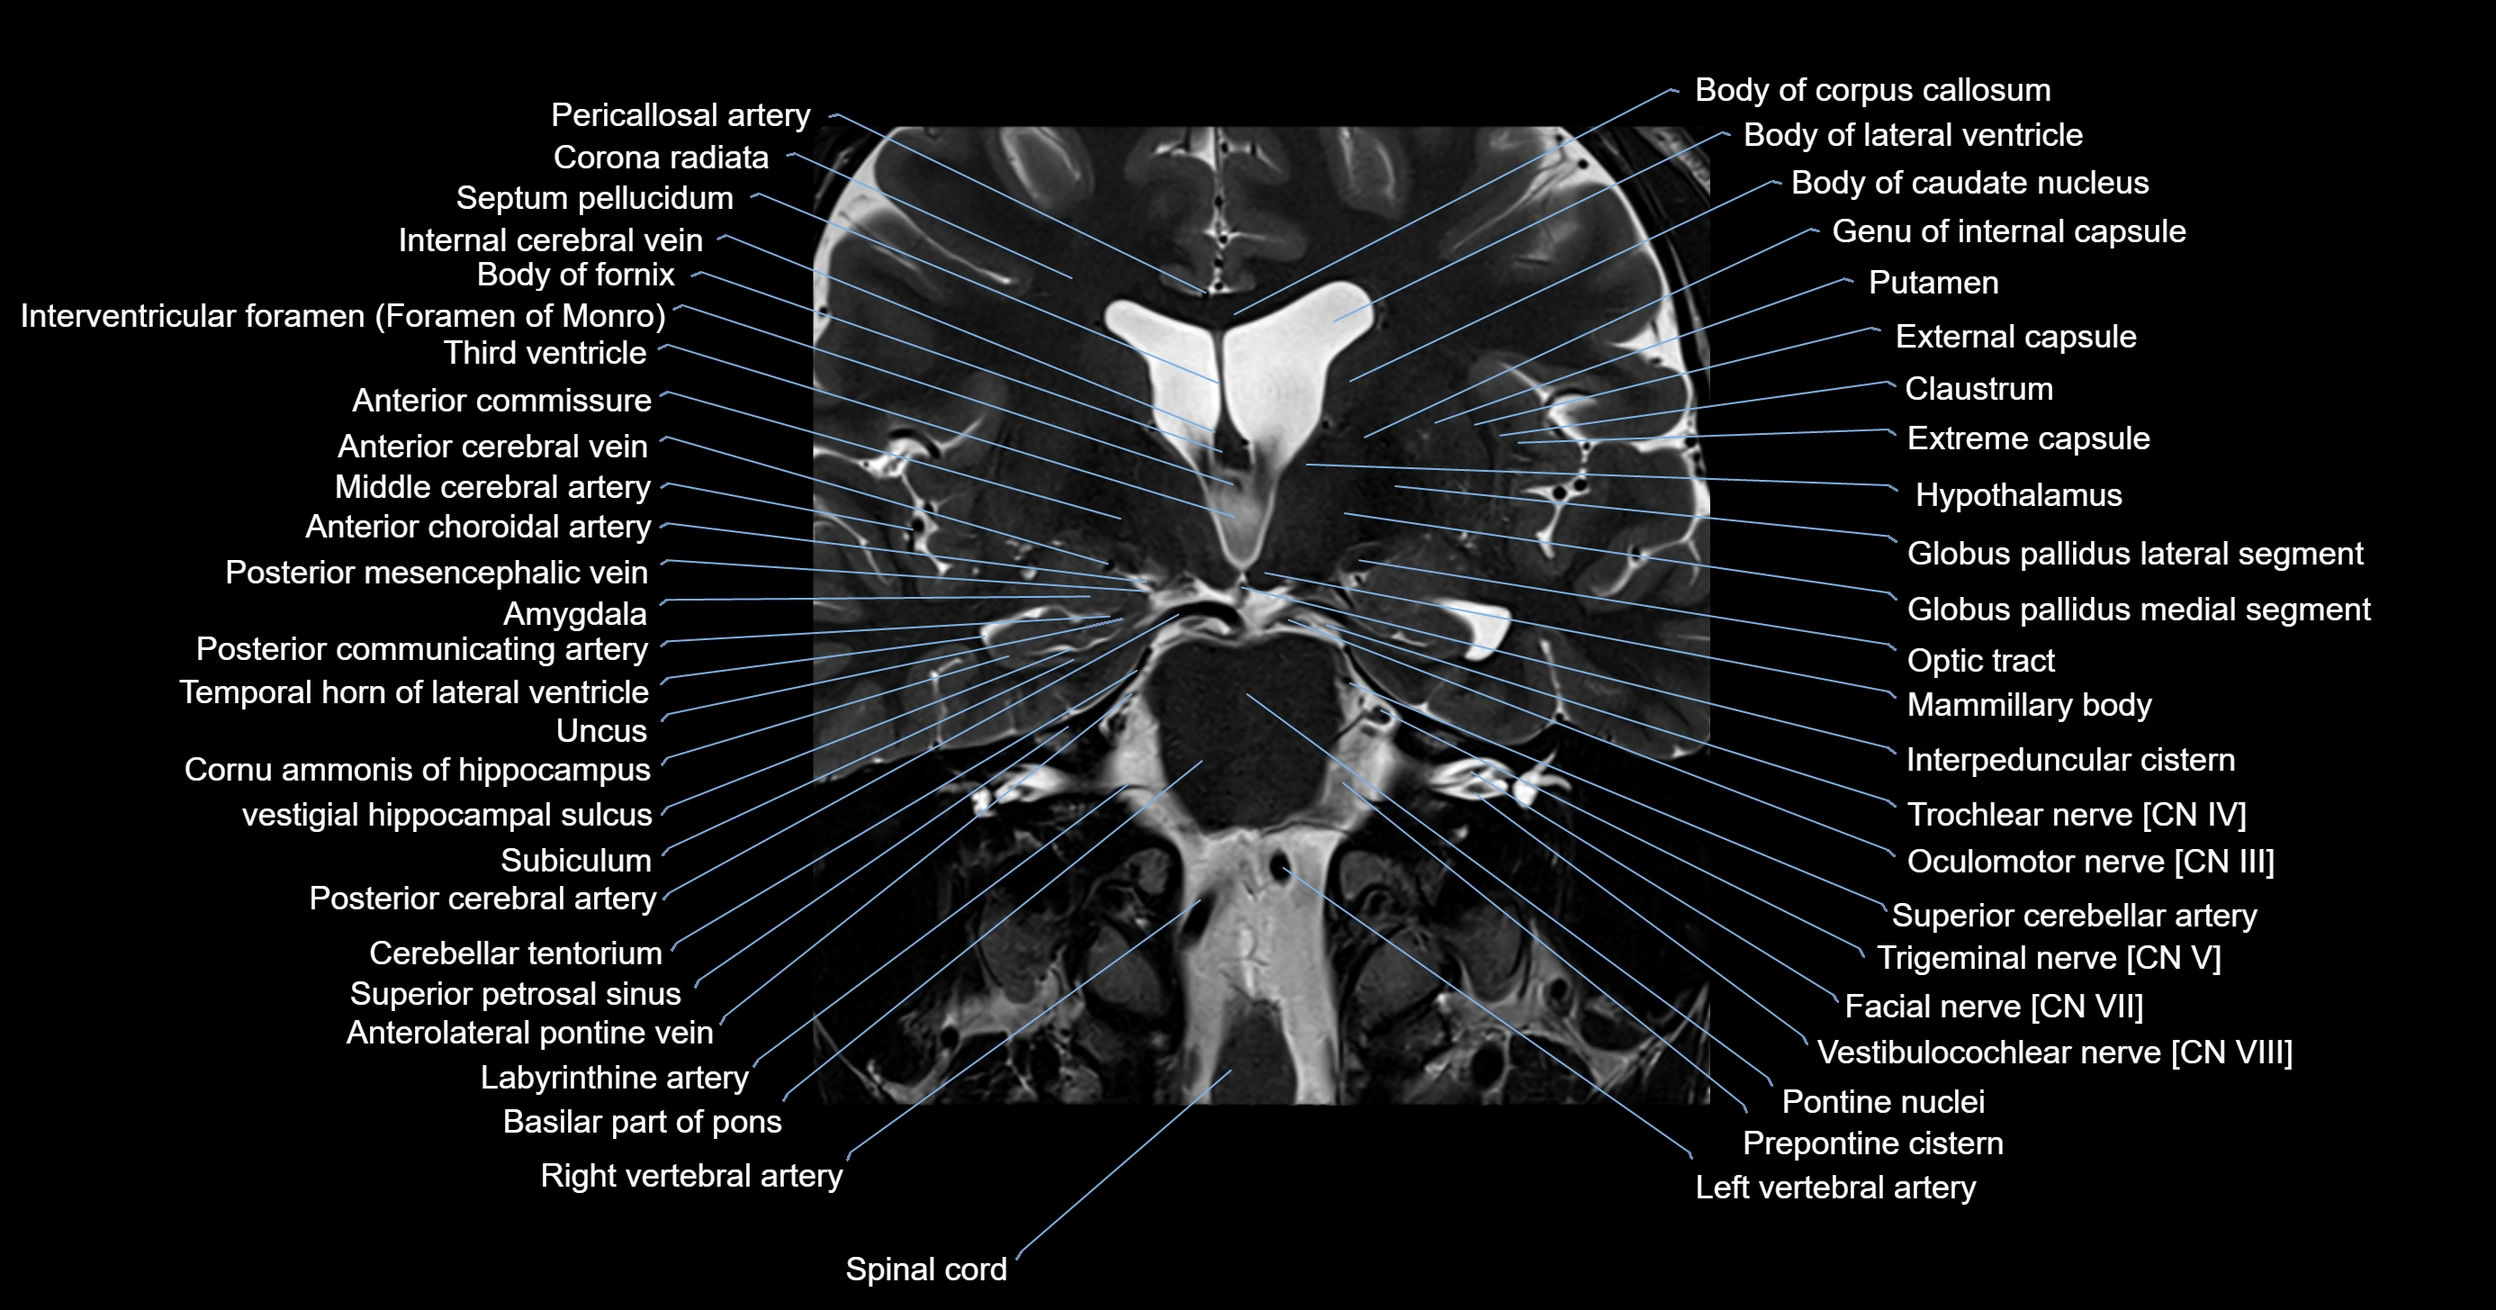

- Amygdala

- Body of caudate nucleus

- Body of fornix

- Claustrum

- Column of fornix

- External capsule

- Extreme capsule

- Globus pallidus external segment

- Globus pallidus internal segment

- Hypothalamus

- Internal cerebral vein

- Interpeduncular Cistern

- Interventricular foramen

- Labyrinthine artery

- Left Vertebral Artery (Intracranial Part)

- Left vertebral artery

- Mammillary body

- Middle cerebellar peduncle

- Oculomotor Nerve (Cranial Nerve III)

- Optic tract

- Petrosal vein

- Pons (basilar portion)

- Pontine nucleus

- Posterior cerebral artery

- Posterior communicating artery

- Prepontine cistern

- Spinal cord

- Superior cerebellar artery

- Superior cerebellar peduncle

- Superior petrosal sinus

- Temporal horn of lateral ventricle

- Thalamus

- Transverse temporal sulcus

- Trigeminal nerve (Cranial nerve V)

- Trochlear nerve (Cranial nerve IV)

- Uncus

- Vestibulocochlear nerve (Cranial nerve VIII)